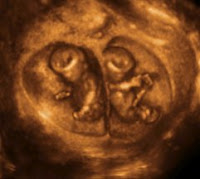

İkİz Gebelİk

Çoğul gebelikler aynı adet döngüsü içinde birden fazla yumurta hücresinin ayrı ayrı döllenip gelişmeye başlamasıyla (Çift yumurta ikizi = dizigotik) veya tek bir yumurta hücresinin döllenme sonrasında iki veya daha fazla eşit hücreye bölünmesi ve bölünen hücrelerden her birinin ayrı ayrı embriyolar halinde gelişmeye devam etmesiyle (Tek yumurta ikizi = monozigotik) ortaya çıkan gebeliklerdir. Bebek sayısının ikiden daha fazla olduğu durumlarda bebekler ayrı ayrı yumurta hücrelerinden köken alabilecekleri gibi, tümü tek yumurta hücrtesinden köken almış olabilir.

Çoğul gebelikler arasında en sık olarak ikiz gebelikler görülmektedir. İkiz gebelikler doğal yollar ile oluşmuş her 85 gebeliğin 1'inde gerçekleşmektedir. Tüm ikiz gebeliklerin üçte ikisi çift yumurta ikizi şeklinde, üçte biri ise tek yumurta ikizi şeklinde ortaya çıkarlar.